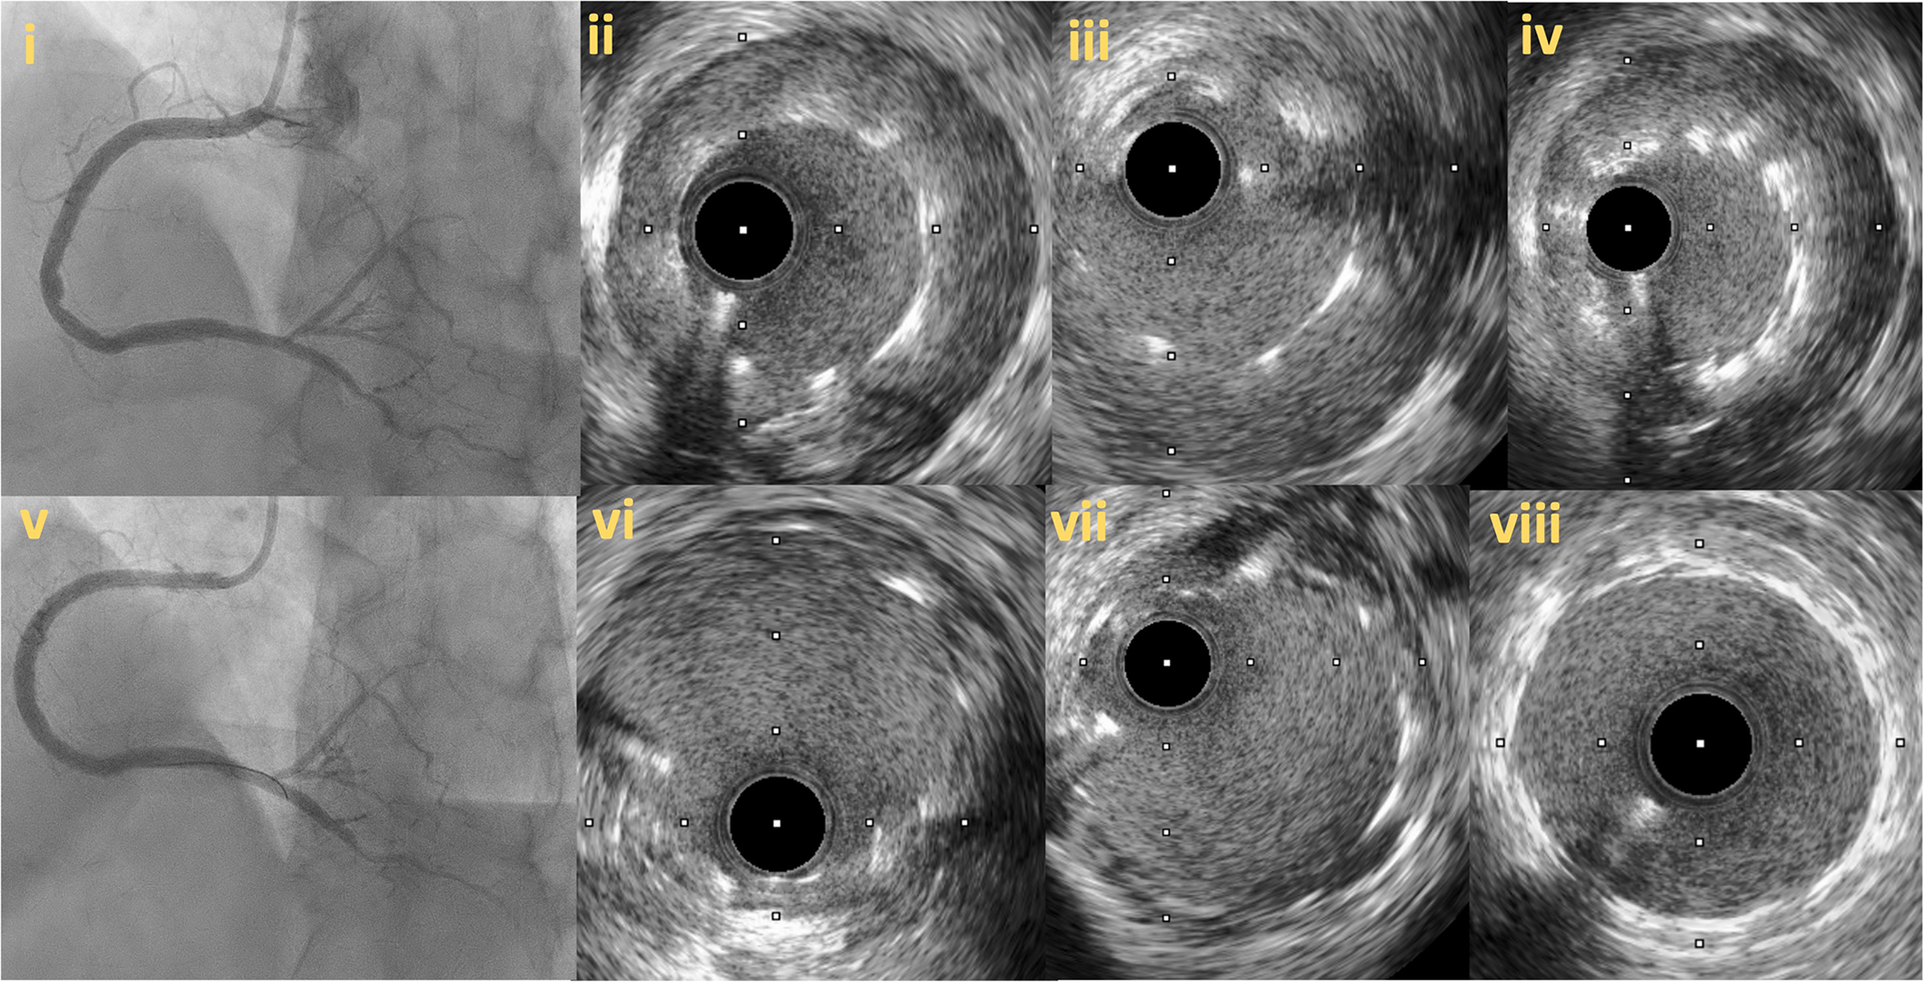

Figure 10

Intravascular imaging (IVUS) guided chronic total occlusion (CTO) percutaneous coronary intervention; (A) initial angiography with contralateral injections to define CTO lesion characteristics; (B) successful antegrade wire crossing; (C) final angiographic result after IVUS guided drug eluting stent (DES) implantation; (D) distal landing zone with reference cross sectional area and diameter estimated at 3 mm; (E) CTO segment cross-sectional area and reference diameter estimated at 4.5 mm; (F) proximal landing zone with reference cross sectional area and diameter estimated at 4.5 mm. The overall lesion length requiring stent coverage from distal landing zone was estimated at 65 mm and therefore two overlapping DES 3.0 × 38 mm and 4.0 × 38 mm were successfully implanted and post-dilated with 3.5 and 4.5 mm non-compliant balloons based on media to media reference diameters as per IVUS measurements; (G) distal stent cross-sectional area with excellent absolute (>5.5 mm2) and relative expansion (>100%); (H) proximal stent cross-sectional area with excellent relative expansion (>100%). Used with permission by Elsevier. Kalogeropoulos AS, Alsanjari, O, Davies, JR. et al. Impact of Intravascular Ultrasound on Chronic Total Occlusion Percutaneous Revascularization. Cardiovasc Revasc Med. 2021; 33:32–40.